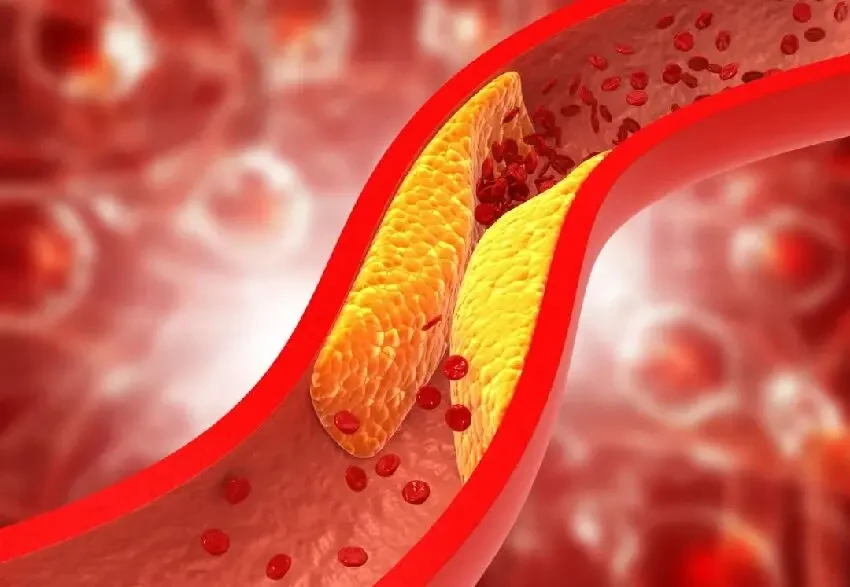

血管壁光滑,無異常隆起:血管壁光滑,血液便能毫無阻礙地奔騰向前。

一旦血管壁出現異常隆起,這可是血管病變的信號,比如動脈粥樣硬化斑塊的形成。

這些斑塊就如同河道里的淤泥,越積越多,最終堵塞河道。

當體檢報告中的總膽固醇>5.18 mmol/L 且 LDL - C>3.37 mmol/L 時,需警惕動脈粥樣硬化風險,建議結合頸動脈超聲綜合評估。

這可不是簡單的數字超標,背後隱藏的是血管健康的危機,必須引起重視。

快停下!高油、高鹽、高糖的食物,就像血管的 「慢性毒藥」。